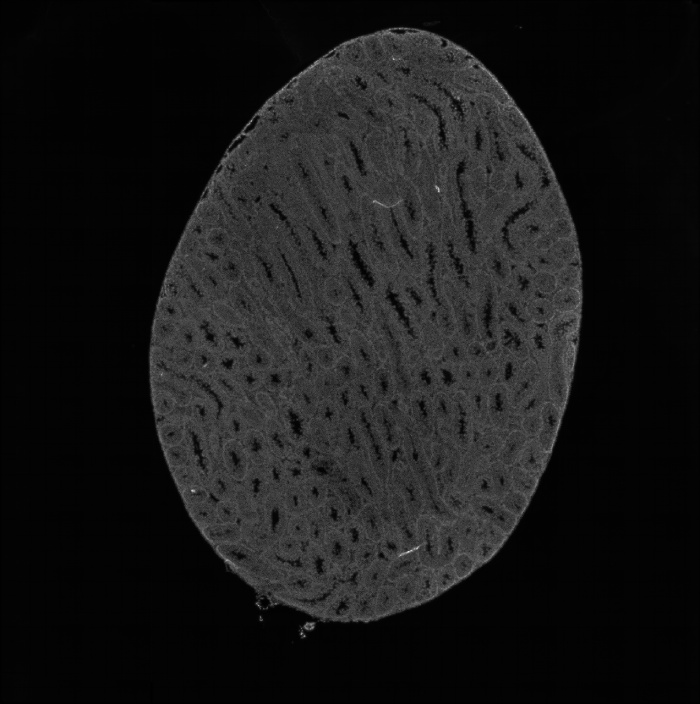

組織切片HE染色圖

圖1 組織切片HE染色圖